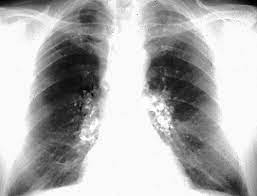

En las radiografías de tórax (CXR), estas máculas de carbón se presentan como pequeñas opacidades difusas, especialmente notables en las regiones pulmonares superiores. La distribución predominante de estas opacidades en los lóbulos superiores es característica de la neumoconiosis del trabajador del carbón y refleja la tendencia del polvo a acumularse en estas áreas debido a la dinámica de ventilación y la gravedad.

Sin embargo, a medida que la exposición al polvo de carbón continúa y la enfermedad progresa, puede desarrollarse la neumoconiosis complicada del trabajador del carbón, también conocida como fibrosis masiva progresiva (FMP). En esta etapa, se produce una conglomeración de las máculas de carbón y una significativa contracción y fibrosis en las zonas pulmonares afectadas, principalmente en los lóbulos superiores. La progresión de la enfermedad lleva a la formación de grandes áreas de fibrosis que se asemejan a las características radiográficas observadas en la silicosis complicada, otra forma grave de neumoconiosis en la que también se observa una fibrosis masiva y progresiva.

La neumoconiosis complicada del trabajador del carbón se manifiesta en las radiografías de tórax por la presencia de grandes opacidades conglomeradas y una fibrosis más pronunciada. Esta progresión puede resultar en una notable disminución de la función pulmonar, síntomas clínicos como disnea y tos crónica, y una reducción en la calidad de vida del paciente.

En términos radiográficos, un hallazgo distintivo de la silicosis es la calcificación de la periferia de los ganglios linfáticos hilares, conocida como calcificación de «cáscara de huevo». Este patrón radiográfico es un marcador característico que sugiere fuertemente la presencia de silicosis, aunque no es observado en todas las presentaciones de la enfermedad. La calcificación de la cáscara de huevo se refiere a la calcificación de los bordes de los ganglios linfáticos hilares y mediastínicos, que se observa en las imágenes radiográficas y es indicativa de una respuesta inflamatoria crónica prolongada.

En su forma simple, la silicosis suele ser asintomática y las alteraciones en las pruebas de función pulmonar (PFT) rutinarias pueden ser mínimas. Los nódulos silicóticos en esta fase no suelen causar una reducción significativa en la función respiratoria ni producir síntomas clínicos evidentes. Sin embargo, a medida que la enfermedad progresa y se convierte en silicosis complicada, los pacientes desarrollan grandes conglomerados de nódulos en los pulmones, particularmente en las regiones superiores. Esta forma avanzada de silicosis, también conocida como fibrosis masiva progresiva, se acompaña de síntomas como disnea (dificultad para respirar) y una disfunción pulmonar que puede ser tanto obstructiva como restrictiva.